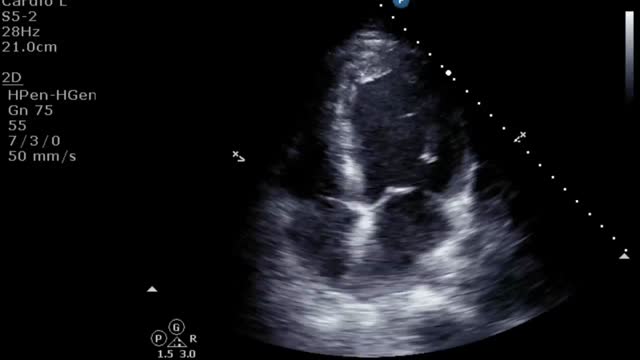

El aumento de la poscarga que condiciona la ECMO, junto con la baja contractilidad ventricular izquierda, puede comprometer la apertura valvular aórtica, pudiendo presentar un cierre precoz de la válvula (suplementario 13) e incluso permanecer cerrada (fig. 3 y suplementario 14).

El destete supone un proceso de descenso gradual (500ml cada 15-20min) del soporte de la ECMO VA de manera que se restablece progresivamente la precarga en el corazón. Para ello el paciente debe estar adecuadamente anticoagulado. Evaluaremos la repercusión hemodinámica (PVC, PAM y diferencial, SvO2, SatO2) y ecocardiográfica (FEVI, IVT, onda E, onda E’ o S’ del anillo mitral lateral) que tiene hasta un nivel (normalmente 1-1,5l/min) que nos indique que el paciente puede tolerar la retirada de la asistencia. Durante esta, evaluaremos que mantiene e incluso aumenta la FEVI por encima del 25-30%, la IVT por encima de 10cm y la onda S’ de más de 6cm/s (fig. 5 y suplementario 22). Junto con ello, también evaluaremos el comportamiento de las cavidades derechas (desplazamiento sistólico del plano del anillo tricuspídeo>16cm, S’>10cm/s y tamaño VD) y la posible aparición de signos de hipertensión pulmonar (aumento de la velocidad pico de la insuficiencia tricuspídea) que predigan un fracaso de VD38–40.

Evaluación ecocardiográfica de destete de paciente con ECMO VA. Ecografía transtorácica e integral velocidad-tiempo (IVT) del tracto de salida del ventrículo izquierdo al reducir flujo (A: 3L/min, B: 2,5L/min, C: 2L/min) de ECMO VA. Obsérvese el aumento del tamaño de la IVT y consecuentemente del volumen sistólico y del gasto cardiaco.